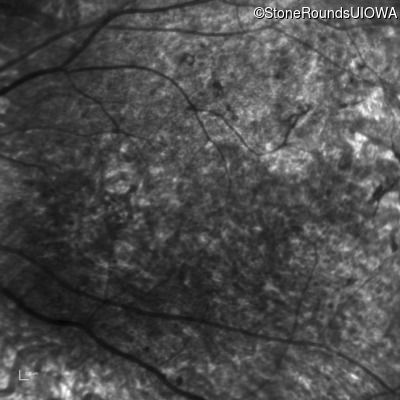

Infrared Fundus Photograph - Right - 5/200

Exemplar